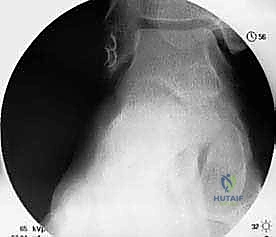

2. التقييم بالمنظار (Arthroscopy) بتقنية 4K:

قبل البدء في إعادة البناء، يقوم الدكتور هطيف بإدخال كاميرا دقيقة جداً (منظار) داخل مفصل الكاحل. تتيح شاشات الـ 4K رؤية تفاصيل المفصل بوضوح مذهل. يتم في هذه الخطوة تنظيف المفصل من أي أنسجة ملتهبة، إزالة الشظايا العظمية أو الغضروفية السائبة، ومعالجة أي تلف في الغضروف ناتج عن عدم الاستقرار المزمن.